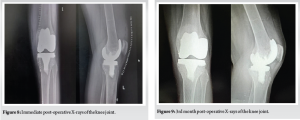

A 17-year-old male with a body mass index of 29.6 presented to our department with complaints of pain over the left knee, difficulty in walking, climbing stairs, squatting, and sitting cross-legged. Detailed history revealed that the patient was diagnosed with ankylosing spondylitis and was prescribed oral steroids for a long duration. He is also diagnosed with clinical depression secondary to the knee disease affliction, and is undergoing pharmacotherapy for the same. He started experiencing pain, locking of the knee in flexion, and difficulty in day-to-day activities, for which he consulted several doctors and was managed conservatively for the same. Despite the ongoing treatments, the patient was not relieved of his symptoms and came to our center for further management. Physical examination revealed lateral joint line tenderness, restricted and painful range of motion with flexion up to 100°. Pre-operative recorded Oxford Knee Score (OKS) was 16, Knee Society Scoring (KSS-K) system of 47, and KSS-F (Functional) of 45. There was no evidence of laxity or instability. On radiological examination, the left knee anteroposterior (AP), lateral, and skyline X-ray (Fig. 1) revealed femoral lateral condyle and trochlea articular surface irregularities with sclerotic changes, subchondral collapse, reduced joint space, and the presence of a loose body in the lateral femoral gutter. Cystic lesions were also noted in the medial femoral condyle with marginal osteophytes. Secondary osteoarthritic changes were noted predominantly in the lateral compartment. The standing X-ray scanogram revealed a valgus alignment of the limb (Fig. 2).

A midline incision using the conventional medial parapatellar approach to the knee was made. Intraoperative examination revealed fissuring and loss of articular cartilage with alteration in the morphology of both medial and lateral femoral condyles (Fig. 6). Large articular cartilage dehiscence with defect noted in the lateral femoral condyle (Fig. 7). A loose bodymeasuring around 5 × 3 cm was retrieved from the lateral femoral gutter. Intraoperative tissue samples were sent for histopathological examination, which later confirmed the diagnosis of chronic synovitis with bone osteonecrosis. Femoral and tibial marker pin inserted and bony registration done. Gap balancing using a robotic-assisted system (CUVIS® Robotic Joint System) was done. The cuts were performed according to the gap-balancing principles to attain perfect mechanical alignment and balance mediolateral gaps in all ranges of movements from full extension to full flexion, which were assessed in real-time by the robot. The trial prosthesis was inserted, and kinematics were tested, including patellofemoral joint tracking. The final implantation was done using cemented femoral components of size H, tibial components of size 5, and a fixed bearing tibial insert of 9 mm thickness (Maxx Freedom TKA System, Meril®, IN). The mediolateral and AP stability, along with patella tracking, were ascertained during trial and after final implantation. No major complications, such as infection, wound breakdown, deep venous thrombosis, or vascular injury, occurred. The post-operative radiograph revealed a well-aligned and well-fixed prosthesis (Fig. 8). The patient was made to walk comfortably on the same day and was very satisfied with the final outcome. At the latest 3rd-month follow-up, the radiographs showed a well-fixed prosthesis (Fig. 9). The patient had a stable knee with a good range of motion of 0–110° (Fig. 10) with OKS of 42, KSS-K score of 88, and KSS-F score of 90, which had improved significantly compared to the pre-operative recorded score.